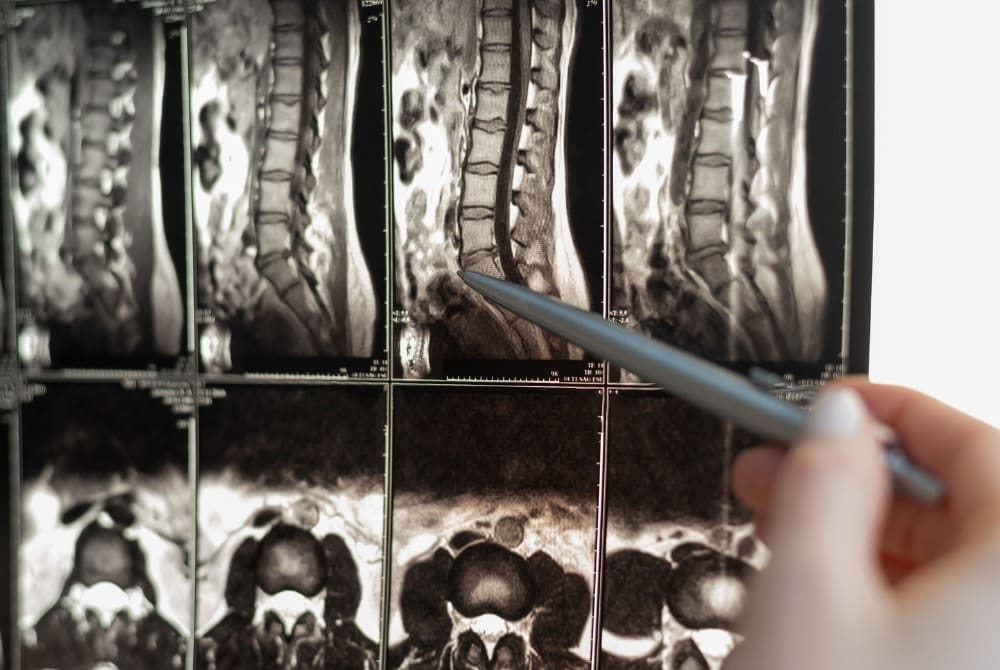

Lumbar discography is a diagnostic procedure used to evaluate and pinpoint the source of lower back pain. During this procedure, a contrast dye is injected into one or more intervertebral discs in the lumbar spine, followed by X-ray or fluoroscopy imaging to visualize the disc’s structure and identify any abnormalities.

Next, the doctor injects contrast dye into each disc, one at a time. The dye raises the pressure inside the discs. When this happens, you may feel pressure or pain. If you feel pain, that may be a sign that the disc is diseased. The doctor will take images with the fluoroscope so your discs can be studied carefully.